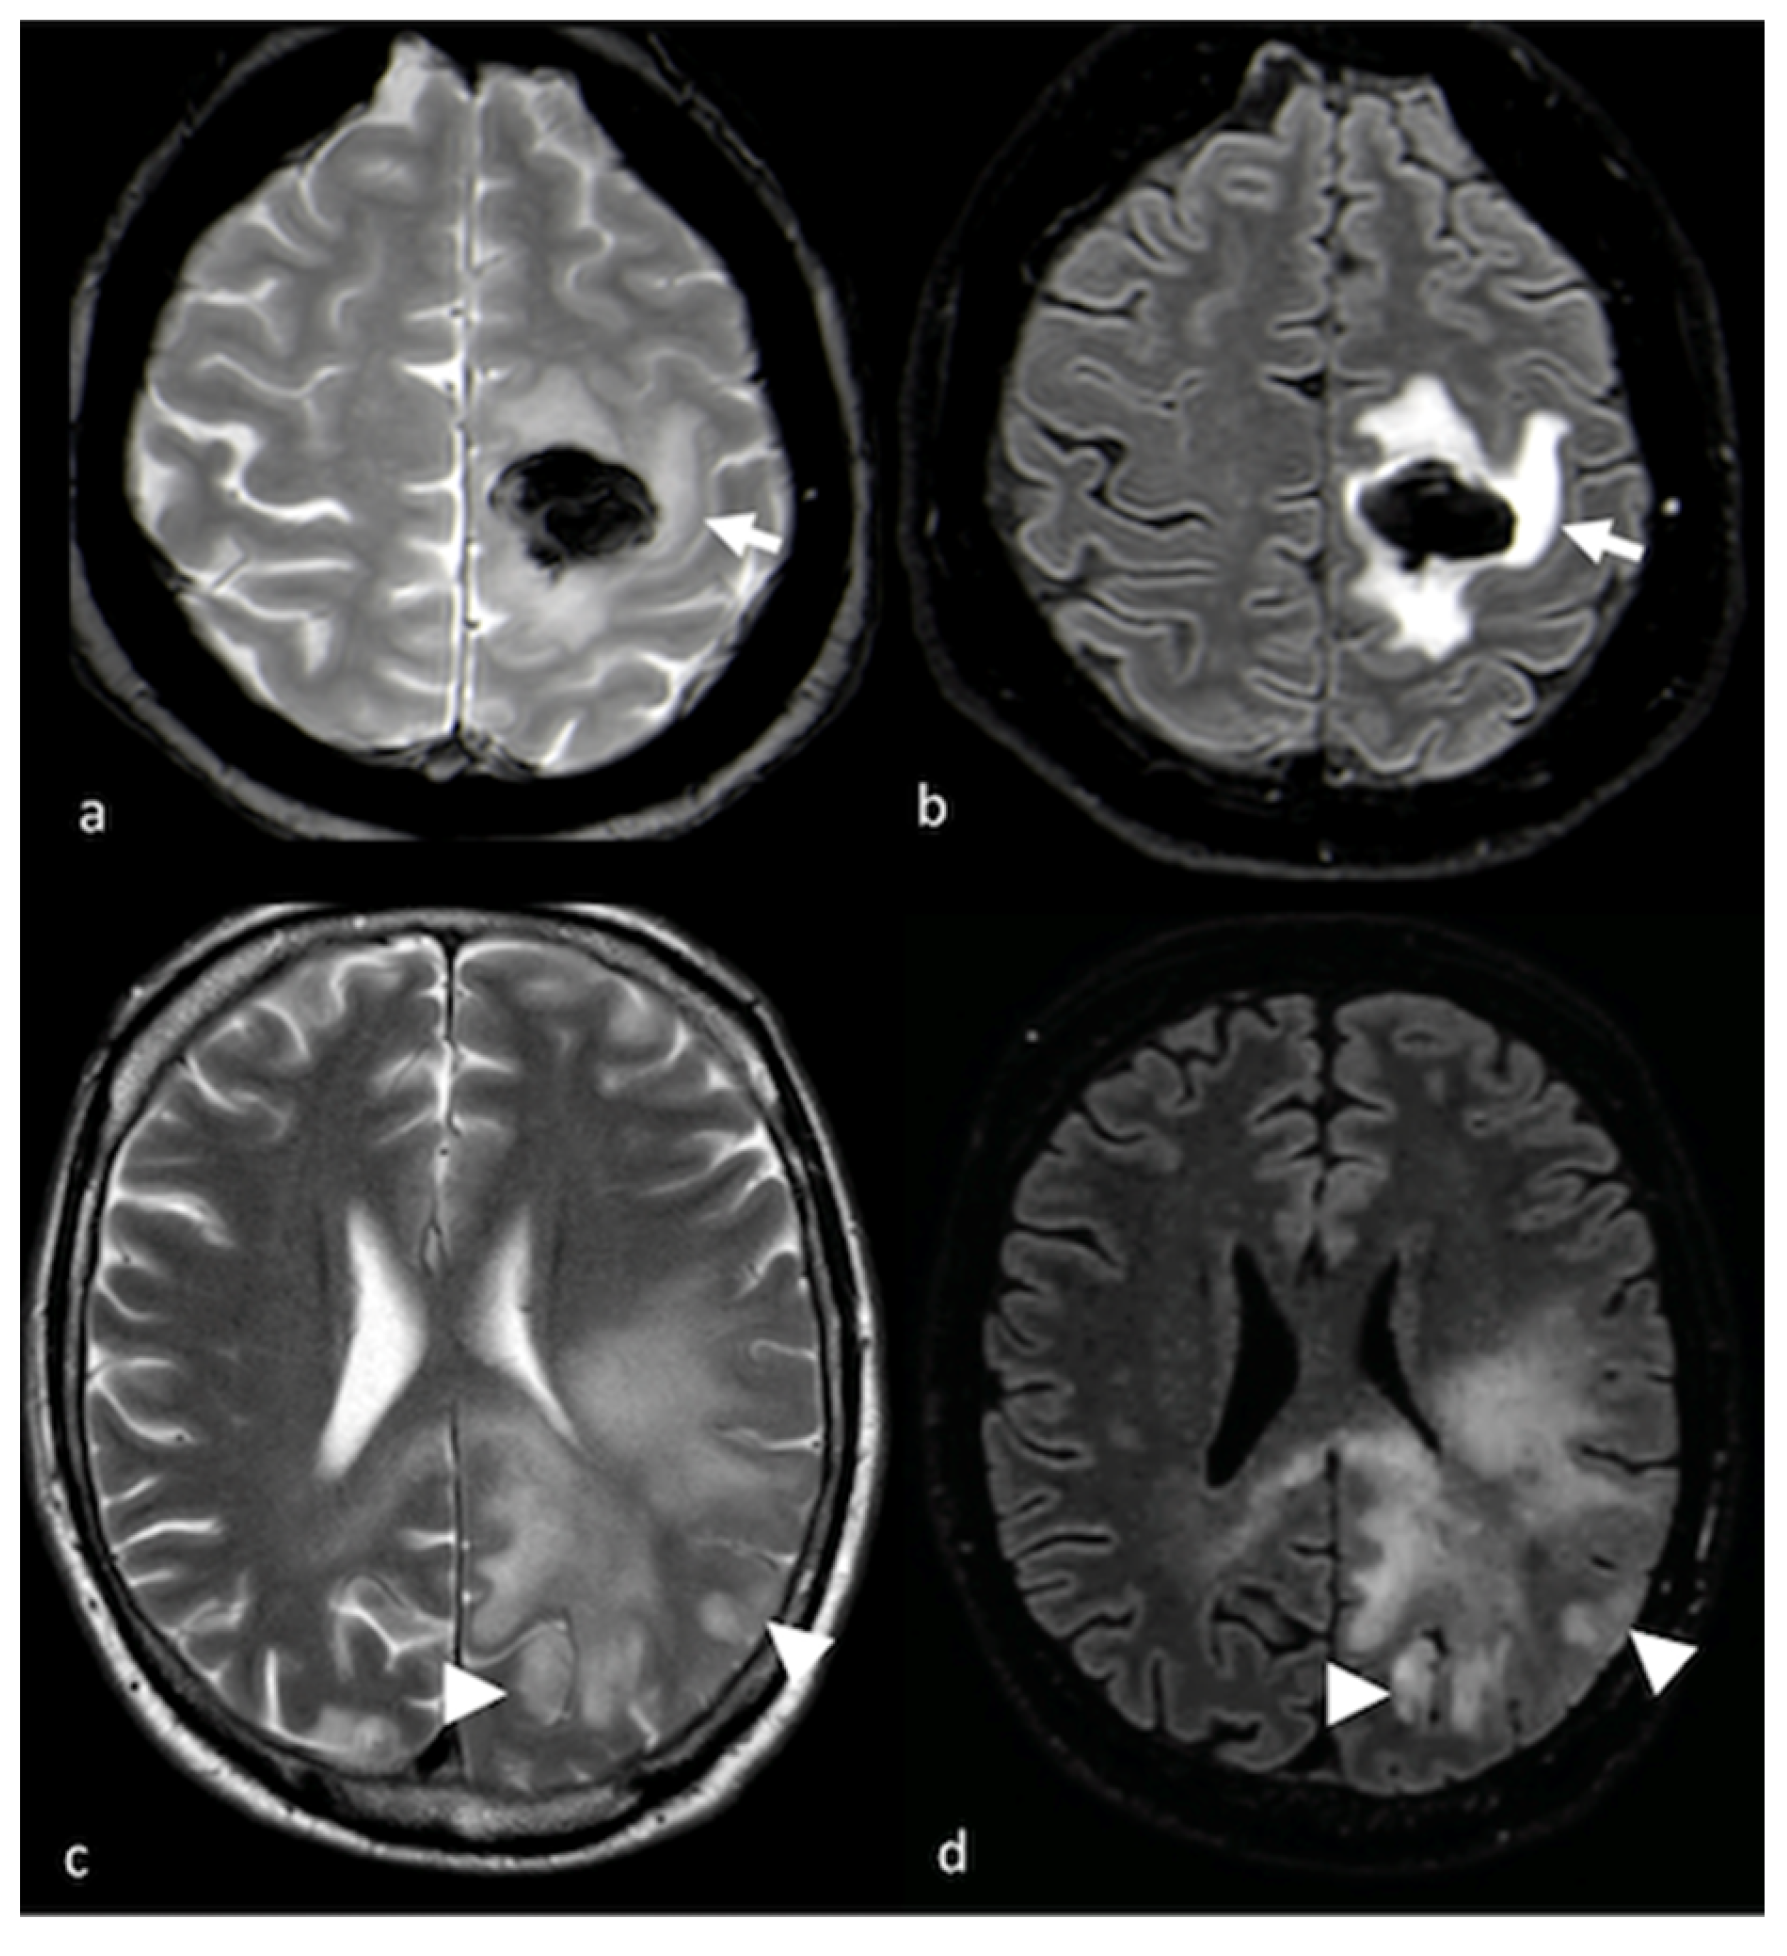

3.1. Conventional MRI

- Tang, Y.M.; Ngai, S.; Stuckey, S. The solitary enhancing cerebral lesion: Can FLAIR aid the differentiation between glioma and metastasis? AJNR Am. J. Neuroradiol. 2006, 27, 609–611. [Google Scholar] [PubMed]

- Wang, P.; Shi, Y.H.; Li, J.Y.; Zhang, C.Z. Differentiating Glioblastoma from Primary Central Nervous System Lymphoma: The Value of Shaping and Nonenhancing Peritumoral Hyperintense Gyral Lesion on FLAIR Imaging. World Neurosurg. 2021, 149, e696–e704. [Google Scholar] [CrossRef]